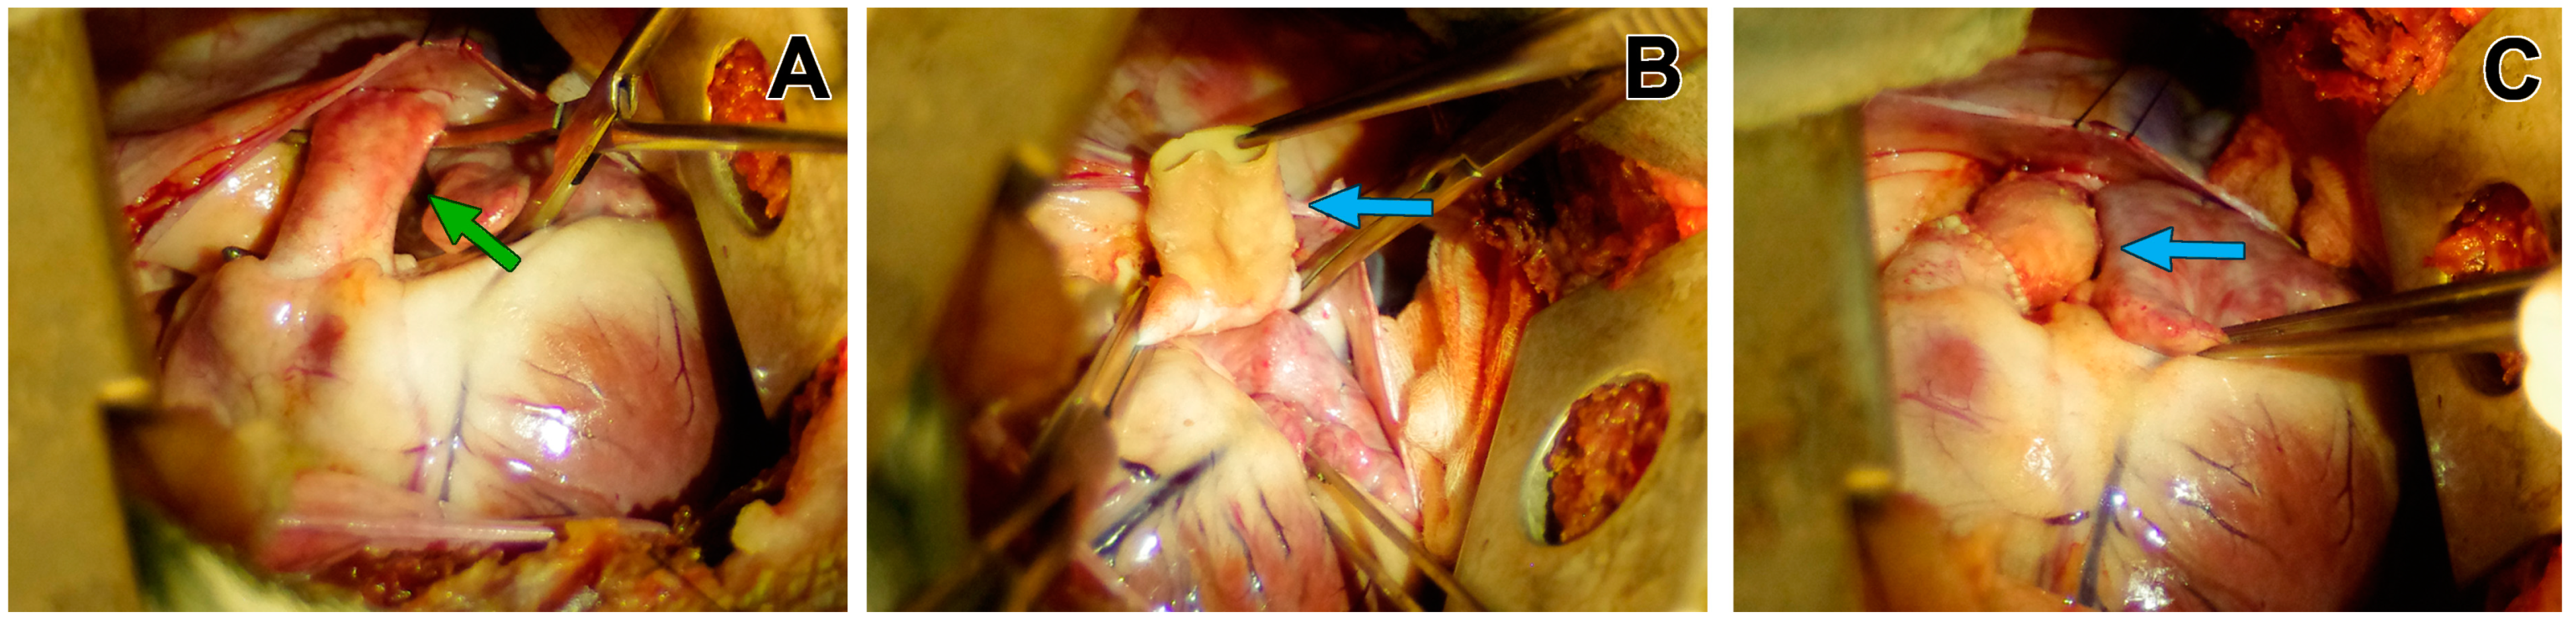

2.3.3. Operative Techniques

3.1. Macroscopic Findings